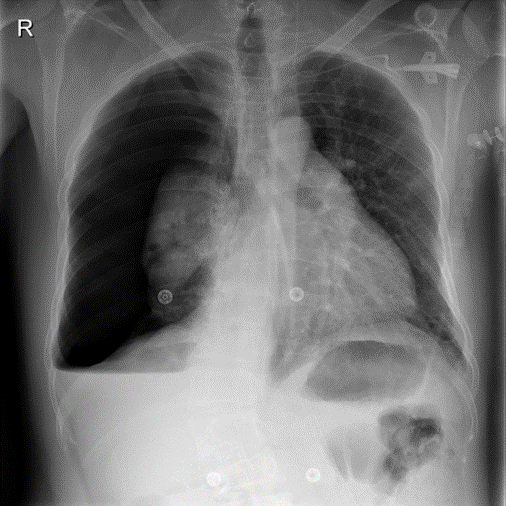

Figure 9: Typical CXRs with pneumonia-like lung opacity from among the top 1,000 CXRs most likely to have an abnormality according to the logarithm posterior probability out of the 13,863 abnormal CXRs. The lesion is indicated with a red arrow if applicable.

Figure 9 shows CXRs suggested to have pneumonia-like lung opacity with the logarithm posterior probability. These CXRs are the top 1,000 CXRs most likely to have an abnormality out of the 13,863 abnormal CXRs.